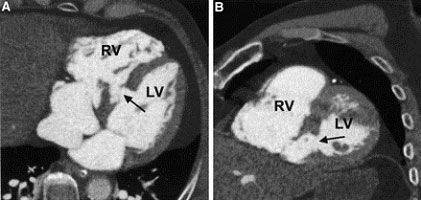

3. острые коронарные синдромы, инфаркты миокарда без подъема ST для оценки поражения венечных артерий сердца [16]. МСКТ позволяет диагностировать возможные осложнения при инфаркте миокарда, к примеру, разрыв межжелудочковой перегородки (рис № 2) [56], а так же развитие аневризмы левого желудочка (рис № 3).

![]() |

| Рис.2. МСКТ сердца. Аневризма в области верхушки левого желудочка (стрелка), кальциноз коронарных артерий. |

| Рис.3. МСКТ сердца. Разрыв межжелудочковой перегородки при остром инфаркте миокарда (стрелка). |